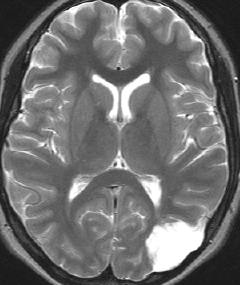

10歳でてんかん発症して難治性になった例

まだ日本にMRIが普及してなかった1988年,10歳でてんかん発作を発症しました。当時は,DNTという病名自体も知られていませんでした。これも典型的なDNTのMRI画像です。20代後半になって,複数の抗てんかん薬で治療を受けていましたが,難治性の発作をしばしば生じていました。発症してすぐに腫瘍摘出をしたほうがよかったのかもしれません。